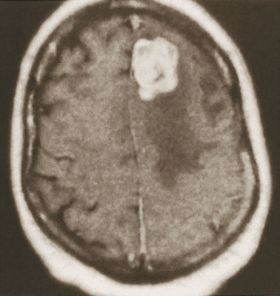

| وذمة (المساحات الأدكن) تحيط بورم مخي ثانوي. | |

إن الوذمة في (الشكل 2) موضعة في منطقة محدودة من الدماغ حول الكتلة الورمية، أما في حال كون الوذمة الدماغية معممة فعندها تُظهر الصور الدماغية إمحاء في الأثلام وأحياناً صِغراً في حجم البطينات الدماغية نتيجة انتباج النسيج الدماغي.